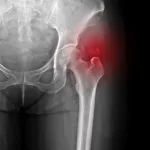

Skolyoz tanısı nasıl koyulur?

Hemen hemen ilk şikayet aile ya da çocuğun farkettiği duruş bozukluğu ya da vücut şekil bozukluğudur. Bu şikayetle hekime başvuran hastaların muayenesi dikkatli bir gözlem ile başlar. Hasta kafa tabanından kalça kıvrımına kadar sırtı görünür halde ayakta gözlenir. Omuz asimetrisi, bel bölgesinde karşı tarafta olmayan cilt kıvrımları, kollar yanda serbest iken her iki tarafta vücut kol mesafesinin aynı olmaması, leğen kemiği asimetrisi ve yandan görünümde göğüs kafesi asimetrisi gibi problemlerin tespit edilmesi; Adam’s Bending Test (öne eğilme testi) de hastanın sırtı yatay düzleme tamamen paralel olacak şekilde eğildiğinde sırtta asimetrik görünüm klinik olarak skolyozu aklımıza getirmelidir. Skolyoz tanısının konulabilmesi için uzun kasetler ile çekilen; kafa tabanı ile uyluk kemiği üst ucunu içine alan ortoröntgenogramlar ile tüm omurga görüntülenmelidir.